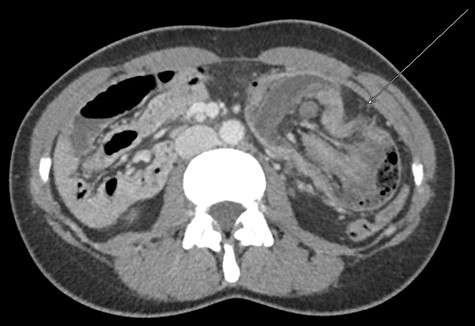

The clinical examination showed a slightly deteriorated condition and a painful distended abdomen with tenderness in all quadrants. There was no rebound pain or palpable masses. Blood tests showed a normal white cell count with a very slight elevation in C-reactive protein (7 mg/l). In the emergency department, the first diagnostic approach with ultrasonography revealed a circular concentric layer, with a maximum diameter of 4–5 cm, highly suspicious of invagination in the left upper quadrant (Fig. 1). The second step was to perform a CT scan with consequent confirmation of the diagnosis. The exam revealed a long ileocolonic intussusception of the ascending colon into the transverse colon, with possible involvement of the terminal ileum; a suspicious strangulation of a superior mesenteric artery branch was postulated (Figs 2 and 3).

CT scan with long ileocolonic intussusception of the ascending colon into the transverse colon, with possible involvement of the terminal ileum, axial plane (white arrow).